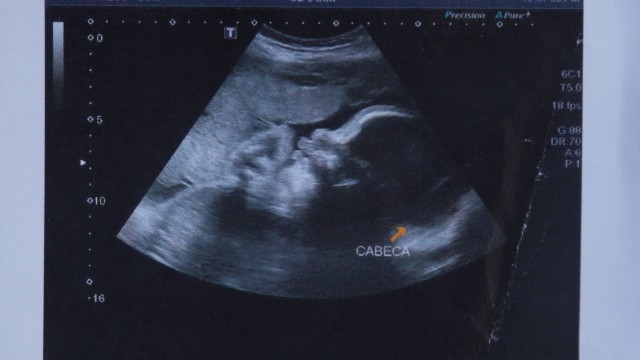

A mãe de Arthur, Claudineia dos Santos Melo, foi baleada no dia 30 de junho, na Favela do Lixão. O bebê, ainda no útero, também foi atingido. Claudineia foi levada para o Hospital Moacyr do Carmo, onde médicos realizaram uma cesárea de emergência.

Dois dias após Arthur ter sido baleado, um laudo médico concluiu que ele estava paraplégico. Depois, no entanto, a equipe médica responsável pelo caso disse que o quadro poderia ser revertido.